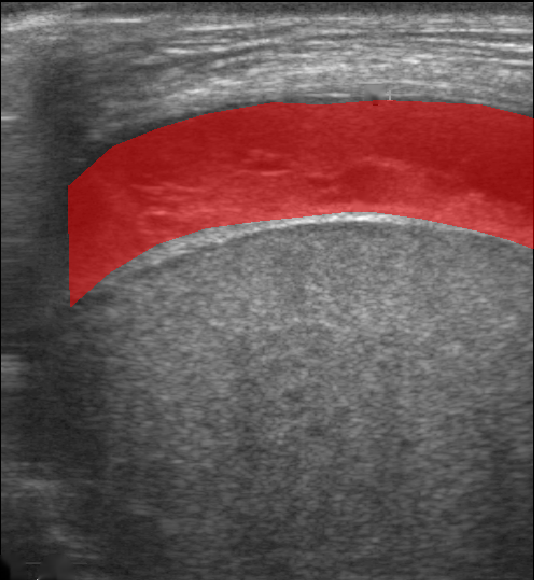

All images in both datasets were manually segmented using the ITK-SNAP software [14] (www.itksnap.org) by a trained observer. Examples of ground truth segmentations are shown in Figure 1 (right column). These segmentations acted as ground truths for training and evaluating the proposed models. Additionally, a second trained observer performed independent segmentations of subsets of 10 random images each from the two datasets. These were used to compute an estimate of inter-observer variability in the manual segmentation process.

Qualitative prediction results of the two proposed models (baseline nnU-Net and nnU-Net with coordinate convolutions) on the two datasets are shown in Figure 2. Tables 1 and 2 summarise the quantitative performances in terms of DSC and area statistics. Histograms of the DSC values are shown in Figure 3. The median DSCs between the manual segmentations on the subsets of 10 images (i.e. the estimates of inter-observer variability) are also shown in Table 1.

Rows 1-2: Dataset A. Rows 3-4: Dataset B.